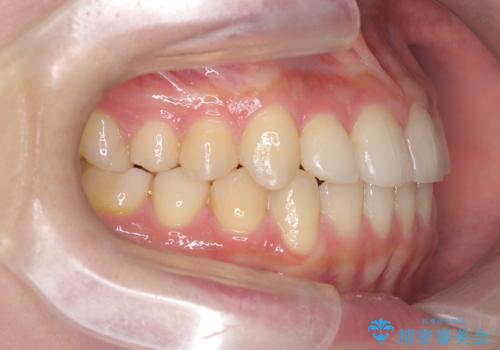

右上の側切歯(前から2番目の歯)が90度程度ねじれている状態でしたが、1月に1回のワイヤー交換できれいに並ぶことができ満足いただけました。

捻れた歯の治療に関しては、ワイヤー矯正の方が仕上がりがきれいに治りやすいです。